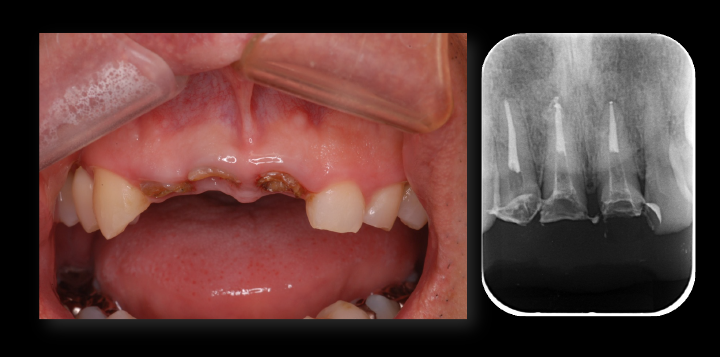

矯正的挺出終了時の口腔内写真及びデンタル

矯正的挺出終了時の口腔内写真及びデンタル写真です。

レントゲン上で目標とする挺出量がかくとくできたので、この段階で歯周形成外科を行うことにしました。

矯正治療開始前及び矯正治療終了時の口腔内写真とレントゲン写真です。

歯肉形成外科の術中所見です。最終的は被せもののイメージを行いながら歯茎と顎の骨の整形を行いました。